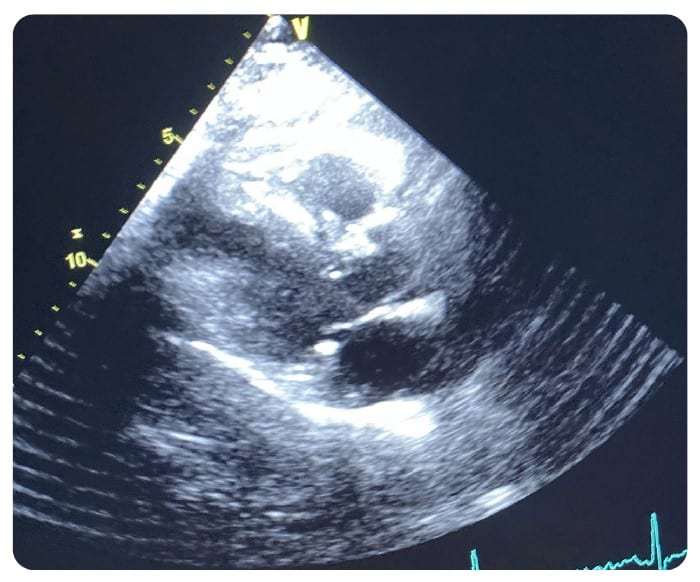

With the proliferation of IoT and wireless technology, the health care setting is even more densely saturated with electronic pollution. Throughout my 30-plus year career in ultrasound, one of the most frequent and most challenging problems to solve has been related to noise artifacts being displayed in an ultrasound image. Typically, these present as axial bands of constant or flashing color in Color Doppler mode. Intense sources of noise can affect 2D imaging in the form of faint gray, semi-axial streaks and/or semi-circular swirls overlaid on the image.